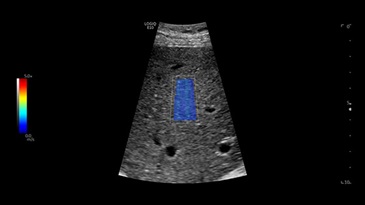

Биопсия печени с использованием насадки Verza